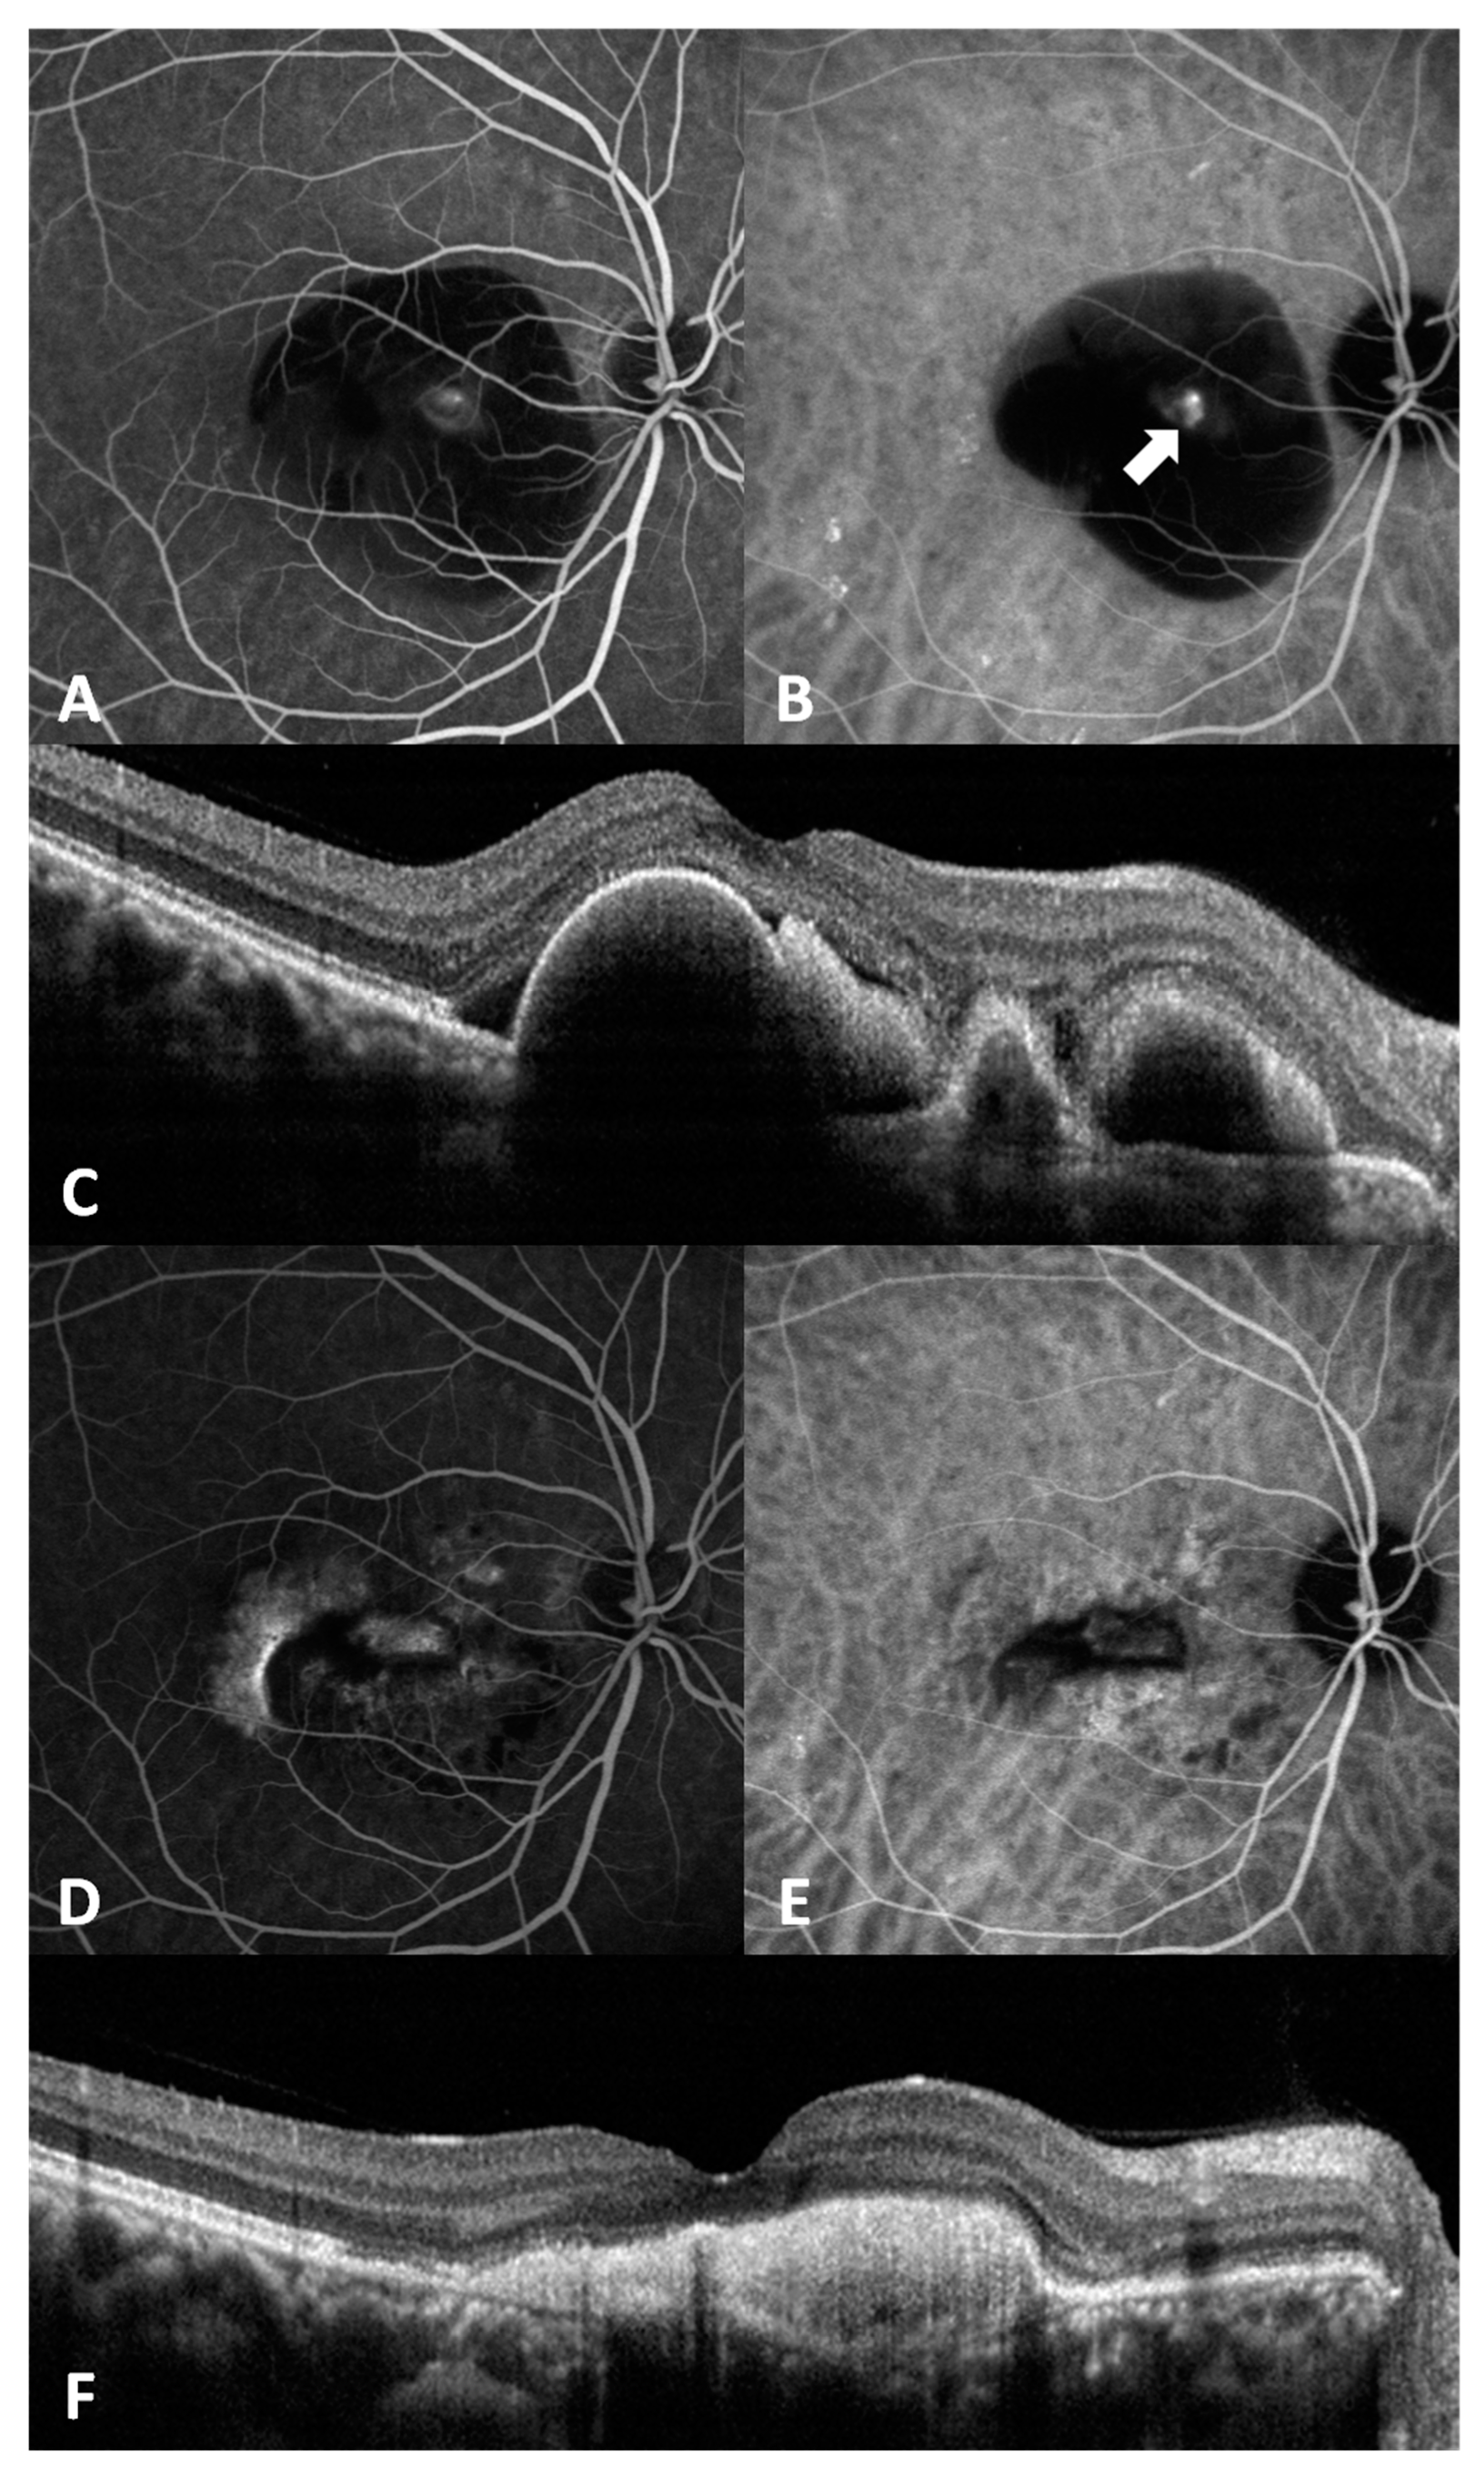

There was a significant correlation of baseline BCVA and final BCVA (r = 0.663, p < 0.001). Younger patients had a better visual outcome (r = 0.328, p = 0.014). Visual outcome was not related to gender, lens status, baseline CRT, retreatment, or complete polyp regression. Retreatment was significantly associated with complete polyp regression at the 3-month period (p = 0.024), but was not associated with baseline characteristics. Figure 3 shows representative images of a case.

Figure 3. This is a 40-year-old man with PCV in the right eye. (AC) were images prior to treatment, and (DF) were images 6 months after IVA/PDT treatment. (A) Fluorescein angiography (FA) showed an occult leakage. (B) Indocyanine green angiography (ICGA) showed a polypoidal lesion (arrow). (C) Optical coherence tomography (OCT) revealed polypoidal lesions and subretinal fluid. (D) FA showed staining without active leakage. (E) ICGA showed complete regression of the polyp. (F) OCT revealed no subretinal fluid, even though pigment epithelial detachment remained.